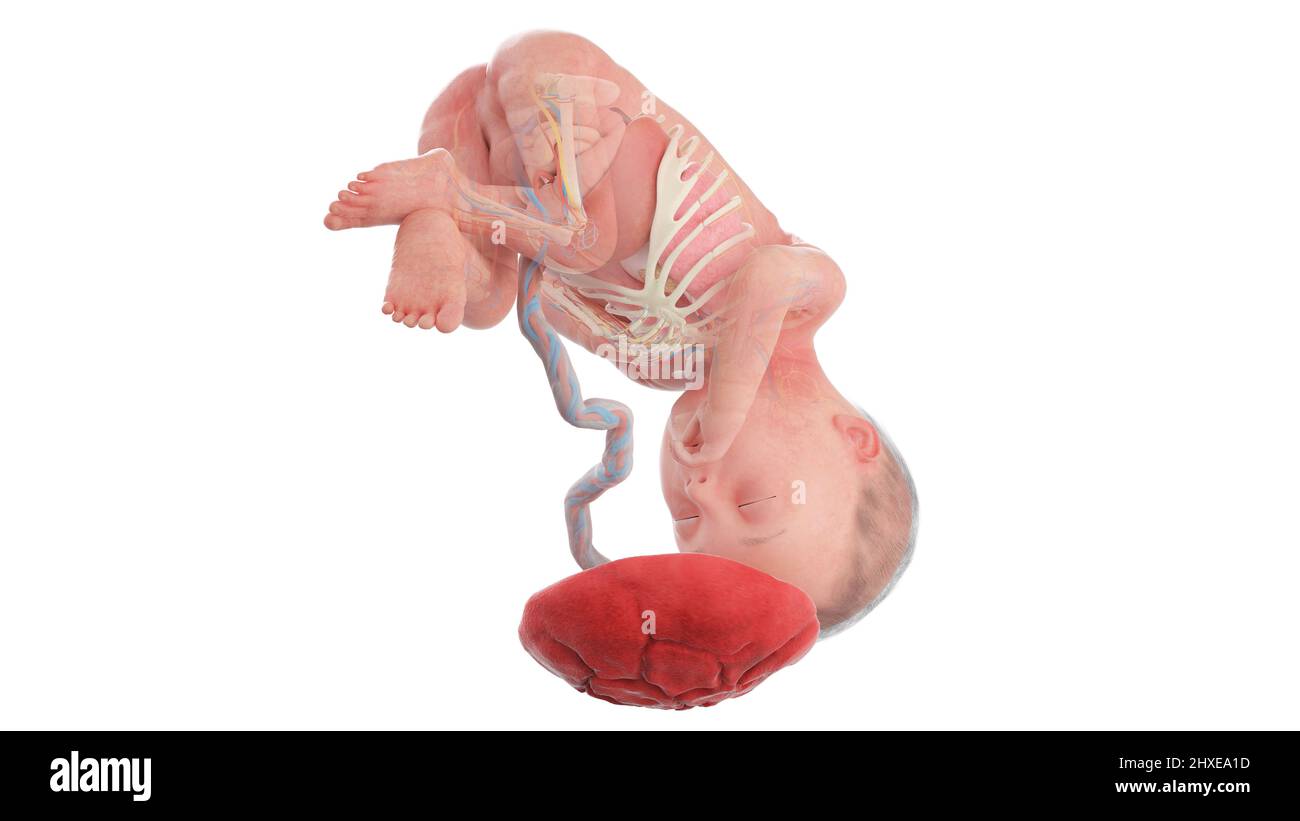

Anatomia del feto umano alla settimana 27, illustrazione Foto Stockhttps://www.alamy.it/image-license-details/?v=1https://www.alamy.it/anatomia-del-feto-umano-alla-settimana-27-illustrazione-image463765847.html

Anatomia del feto umano alla settimana 27, illustrazione Foto Stockhttps://www.alamy.it/image-license-details/?v=1https://www.alamy.it/anatomia-del-feto-umano-alla-settimana-27-illustrazione-image463765847.htmlRF2HXEA1Y–Anatomia del feto umano alla settimana 27, illustrazione

Anatomia del feto umano alla settimana 27, illustrazione Foto Stockhttps://www.alamy.it/image-license-details/?v=1https://www.alamy.it/anatomia-del-feto-umano-alla-settimana-27-illustrazione-image463765833.html

Anatomia del feto umano alla settimana 27, illustrazione Foto Stockhttps://www.alamy.it/image-license-details/?v=1https://www.alamy.it/anatomia-del-feto-umano-alla-settimana-27-illustrazione-image463765833.htmlRF2HXEA1D–Anatomia del feto umano alla settimana 27, illustrazione